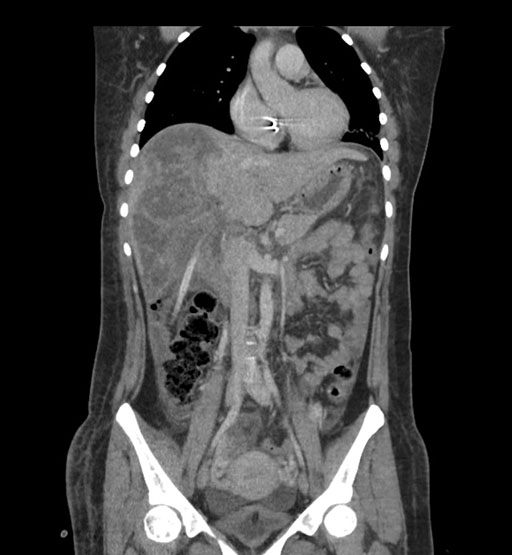

Coronal Arterial

Coronal Venous